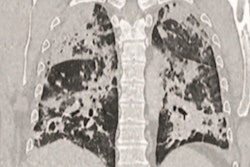

"In our department, four highly suspected patients with COVID-19 underwent FDG-PET/CT in January 2020," wrote the authors, led by Dr. Xiao Zhang from Union Hospital and Tongji Medical College. "PET and SPECT are routine examinations for clinical diagnosis of various diseases and appropriate protective measures should be carried out during this epidemic."

Among the guidelines, Union Hospital's nuclear medicine department requires patients initially to undergo a chest CT scan and a reverse transcription polymerase chain reaction (RT-PCR) test for SARS-CoV-2, the virus that causes the novel coronavirus disease, to make sure patients do not have COVID-19 before they proceed to radiopharmaceutical imaging.